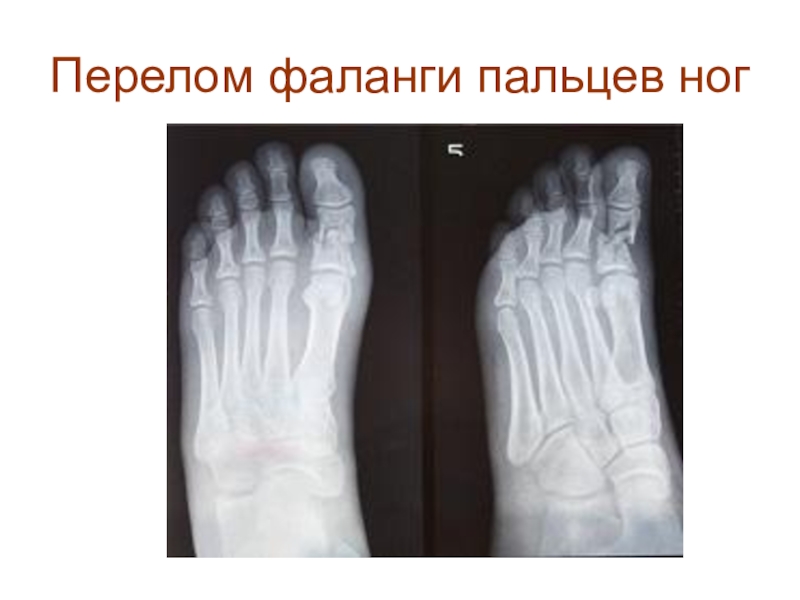

Слайд 41Перелом фаланги пальцев ног

Перелом фаланги пальцев ног